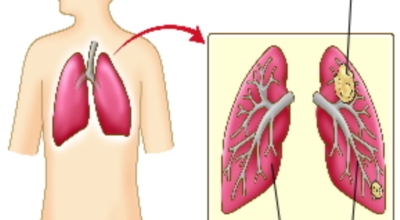

두번째 폐암 초기증상으로 혈담이 있는데 혈담은 쉽게 말해 가래에 피가 섞여나오는 경우입니다. 폐암이 폐 중앙부 기관지 부분과 근접해 있으면 나타나게 되는 혈담은 폐암환자의 25%이상이 경험하는 증상이므로 혹시라도 기침을 할 때 심한가래나 혈담이 섞여 나온다면 즉시 병원에 방문하시기 바래요.